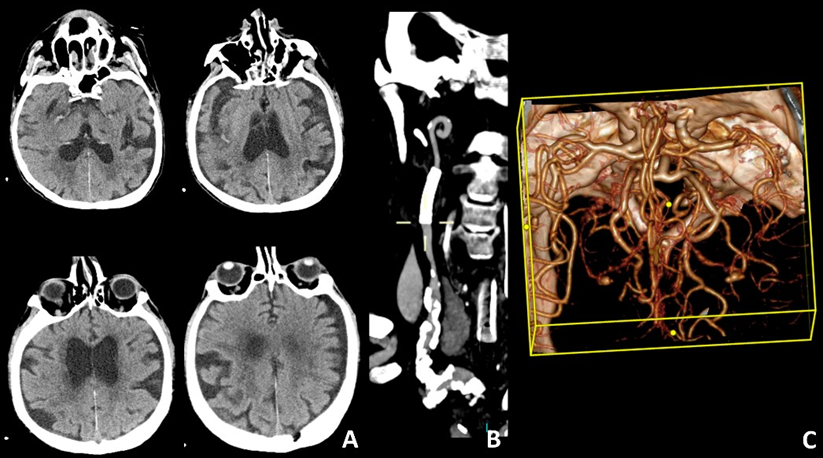

MT was performed using a 4×28 mm stent retriever (Trevo NXT ProVue Retriever, Stryker, CA, USA) in combination with a distal aspiration catheter (Catalyst 6F, Stryker, CA, USA), resulting in complete MCA recanalization (Figures 3A-C). Following the procedure, recurrence of carotid stenosis was observed. To restore and maintain carotid blood flow, a 5×30 mm carotid stent (Wallstent, Boston Scientific, Santa Clara CA, USA) was deployed (Figure 3D). Hemostasis at the carotid access site was achieved with an Axiostat patch (Axio Biosolutions Pvt. Ltd., Gujarat, India) and 5 minutes of light manual compression (Figure 3E). Follow-up CT revealed a small insular infarction and a minimal subarachnoid hemorrhage in the right Sylvian fissure. The carotid stent remained patent, with no complications observed (Figures 4A-C).

Figure 3: Mechanical thrombectomy and carotid stent deployment via direct CCA approach was performed (A-D). Hemostasis of the cervical access was obtained through chitosan-based patch (E).

Figure 4: CT follow-up at 1 week (A-C).